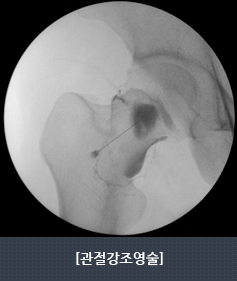

- 관절내의 염증을 가라앉히기 위해 관절강 내 주사 요법을 시행합니다.